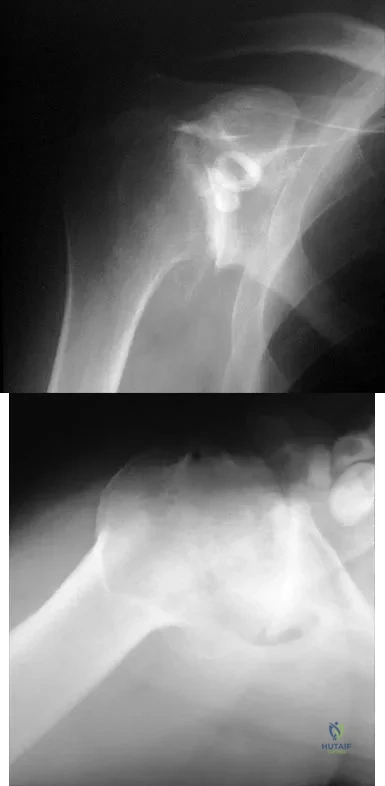

Question 38

A 55-year-old man has had progressive right shoulder pain for the past 2 years. Examination reveals active elevation to 120 degrees, external rotation to 20 degrees, and internal rotation to the sacrum. AP and axillary radiographs are shown in Figures 23a and 23b. Which of the following procedures would result in the most predictable long-term pain relief?

Explanation